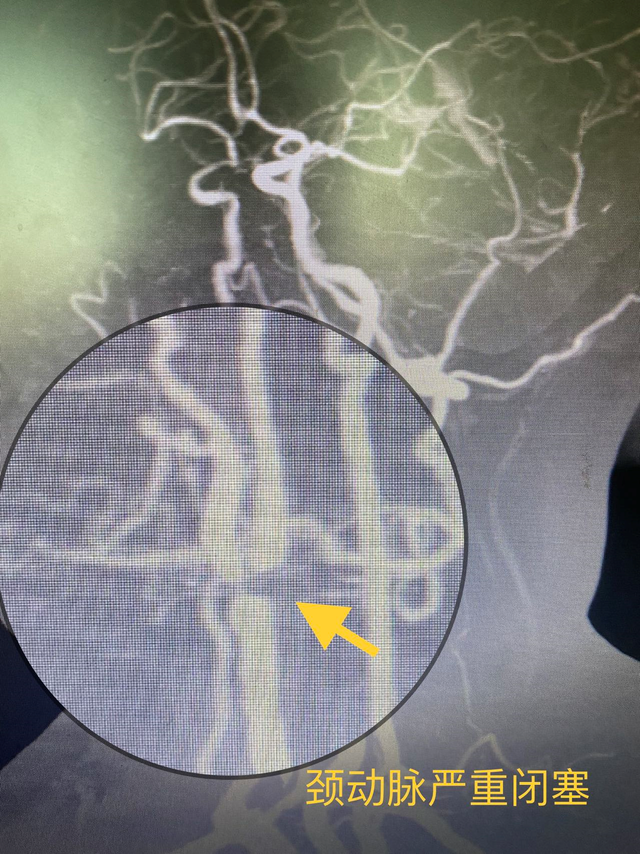

曹大姐在黑朦严重后到湖南省人民医院集团澧县人民医院就诊,通过超声检查发现存在严重的颈动脉病变,右侧颈动脉基本闭塞,继而转诊至介入血管外科。

通过后续的脑部血管及血运评估发现,曹大姐右侧的大脑供血明显比左侧差很多,已出现明显的缺血症状。

湖南省人民医院派驻常德澧县人民医院挂职的颜鹏副院长介绍,曹大姐的眼病其实是一种脑缺血的表现,右侧颈动脉闭塞后可以导致右侧眼动脉供血不足,也可以导致右侧大脑缺血。